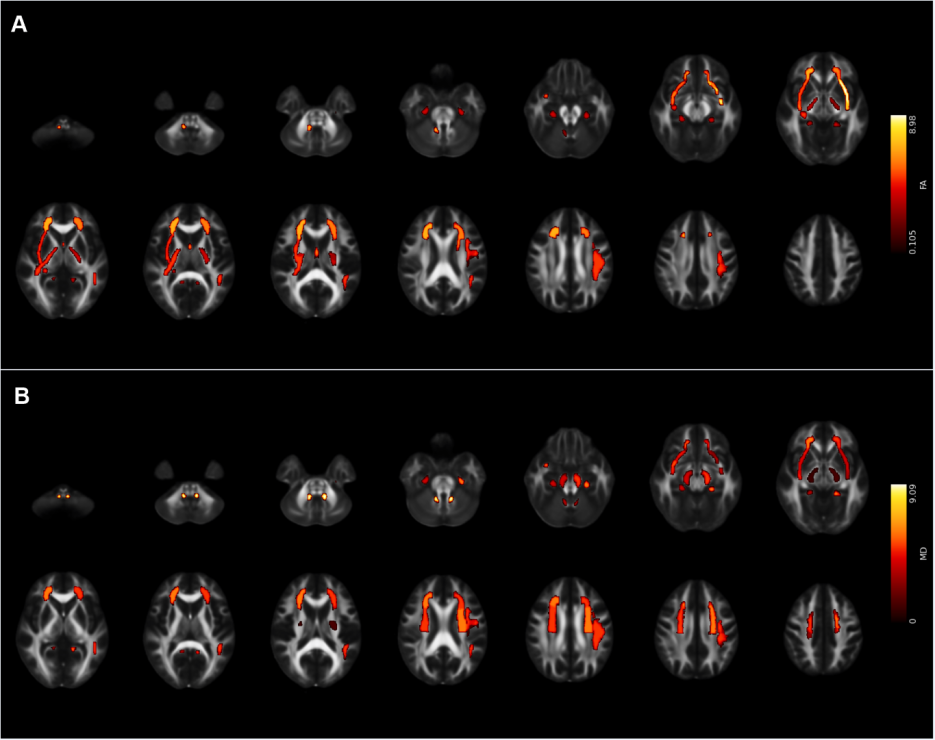

研究團隊招募了49名4-12歲的孤獨癥兒童,實驗組進行了為期12周以小籃球形式為主的團體互動型運動技能學習,對照組則接受常規護理。本研究除了采用自行研發的適用于孤獨癥兒童共同注意任務外,還采用了眼動追蹤技術和磁共振掃描手段,對所有被試進行了基線水平和12周后的數據采集。結果發現,實驗組兒童在經過運動干預后,共同注意顯著提高,線索首次注視時間也到了顯著改善;同時,上縱束、額枕束、扣帶、鉤狀束等聯絡纖維以及放射冠、內囊、外囊、大腦腳等投射纖維完整性顯著增強。

圖1. 干預后,在FA (A)和MD (B)存在顯著交互作用的白質區域